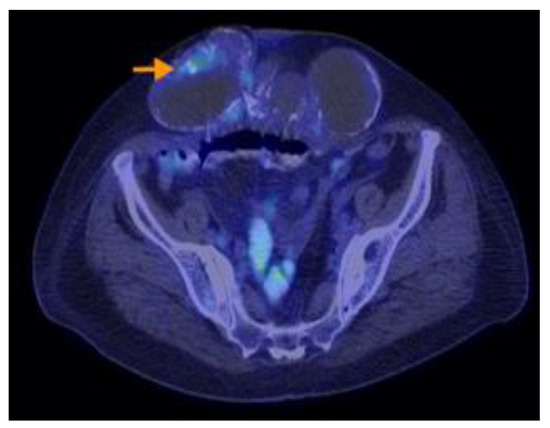

3.2.3. Imaging Findings, Diagnosis, and Differential Diagnosis